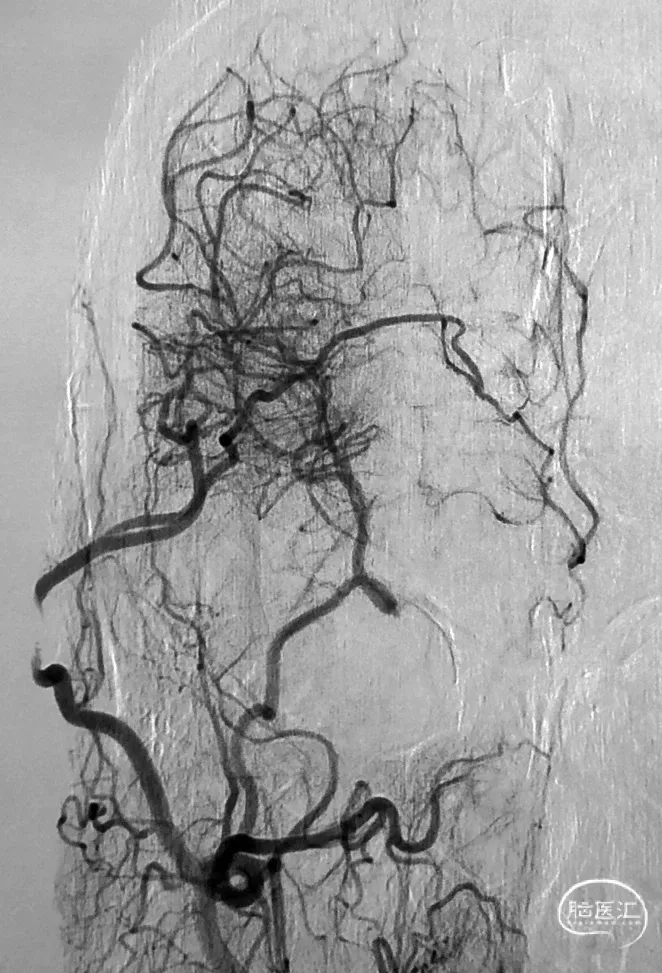

图1 从大脑后动脉(PCA)到大脑前动脉(ACA)的软脑膜侧支;A,椎动脉注射侧位图显示ACA和PCA区域之间的逆行血流(PCA→ACA顶枕支)延伸到皮质边界区;B,经后胼胝体周动脉经中央沟的血供。【7】

2021年,佟志勇等【17】回顾了2019-2020年5例STA-MCA/ACA序贯双吻合术(SDA)治疗MMD的病例,其中3例为STA-MCA-STA-ACA序贯双吻合术(世界首例)。STA中段和M4侧侧吻合,STA末端的额上回A5端侧吻合。使用单定点连续缝合法。术中测量STA压强为74mmHg(1 mmHg=0.133 kPa),A5压强为28mmHg,M4压强为29mmHg,STA侧壁压强为65mmHg。术中STA的切割流量(CF)为15~36ml/min,平均(23.6±7.7ml/min;术后1周STA流量为40~125 ml/min,平均(96.8±31.2)ml/min。术后1周STA血流量为术中CF的4.1倍。

2021年,余冠东和佟志勇等【18】回顾对照研究了STA⁃ACA和STA⁃MCA双吻合术(DBA)与STA⁃MCA双吻合术治疗MMD的疗效。纳入2017-2020年的32例ACA供血区缺血的MMD患者共计41例次手术,分别行STA⁃ACA和STA⁃MCA 双吻合术联合EMS(ACA 组,10例计10例次手术)(2019-2020年)和STA⁃MCA双吻合术联合EMS(MCA 组,25例计31例次手术)。结果显示:ACA组治疗ACA供血区缺血的MMD,桥血管通畅性良好,可获得满意的长期疗效;与MCA组相比,ACA组STA的切割流量指数(CFI)值更高,而两组术后长期疗效相当。

图4 术后2个月头部影像学检查所见:上图,CTA显示,右颞浅动脉与大脑前动脉、右颞浅动脉与大脑中动脉吻合口通畅;

中图1,中图2,右颈外动脉正位和侧位DSA显示,右颞浅动脉与大脑前动脉、右颞浅动脉与大脑中动脉吻合口通畅;

下图,右颈总动脉正位DSA显示,右大脑中动脉M1段烟雾样血管减少。【18】